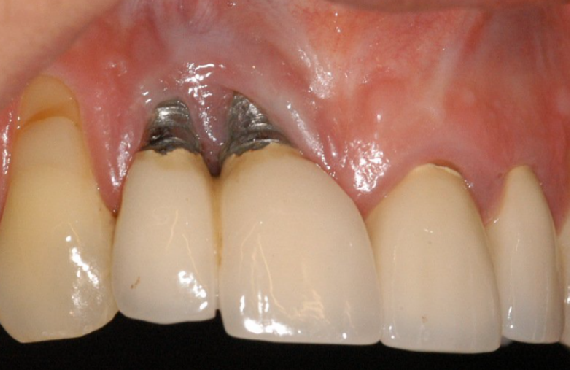

Implants in the Aesthetic Zone

With advances in implantology and our understanding of biology, biomechanics and restorative solutions, expectations from out patients and ourselves are at the highest they have ever been. This lecture will discuss implant placement, hard and soft tissue requirements,...

The Growing Prevalence of Peri-implantitis: Diagnosis and Management of the Disease

Dental implants are highly predictable when treatment protocols are followed. Peri-implantitis is a disease that threatens implant survival long-term. For clinicians, there is no clear consensus on how to prevent and treat this fast-growing problem. This presentation will provide an...